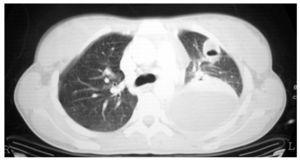

Fig. 3. Tomografía computarizada de tórax.